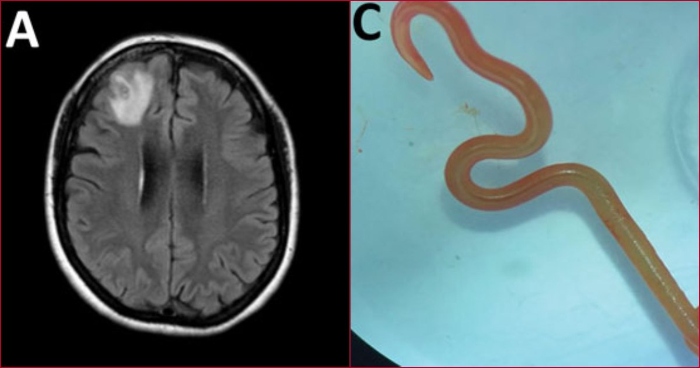

La cirujano Hari Priya Bandi estaba realizando una biopsia a través de un agujero en el cráneo de la paciente de 64 años en el Hospital de Canberra el año pasado cuando usó unas pinzas para extraer el parásito, que medía 8 centímetros.

"Continuó moviéndose con vigor. Todos nos sentimos un poco enfermos". La criatura era la larva de un gusano redondo nativo de Australia que hasta ahora no se sabía que fuera un parásito humano, llamado Ophidascaris robertsi.

La mujer fue ingresada en el hospital después de experimentar olvidos y un empeoramiento de la depresión durante tres meses. Las exploraciones mostraron cambios en su cerebro.

Senanayake dijo que se esperaba que la biopsia cerebral revelara un cáncer o un absceso.

"Esta paciente había sido tratada por lo que era una enfermedad misteriosa que en última instancia pensamos que era una condición inmunológica porque no habíamos podido encontrar un parásito antes y luego, de la nada, apareció este gran bulto en la parte frontal de su cerebro", dijo Senanayake.